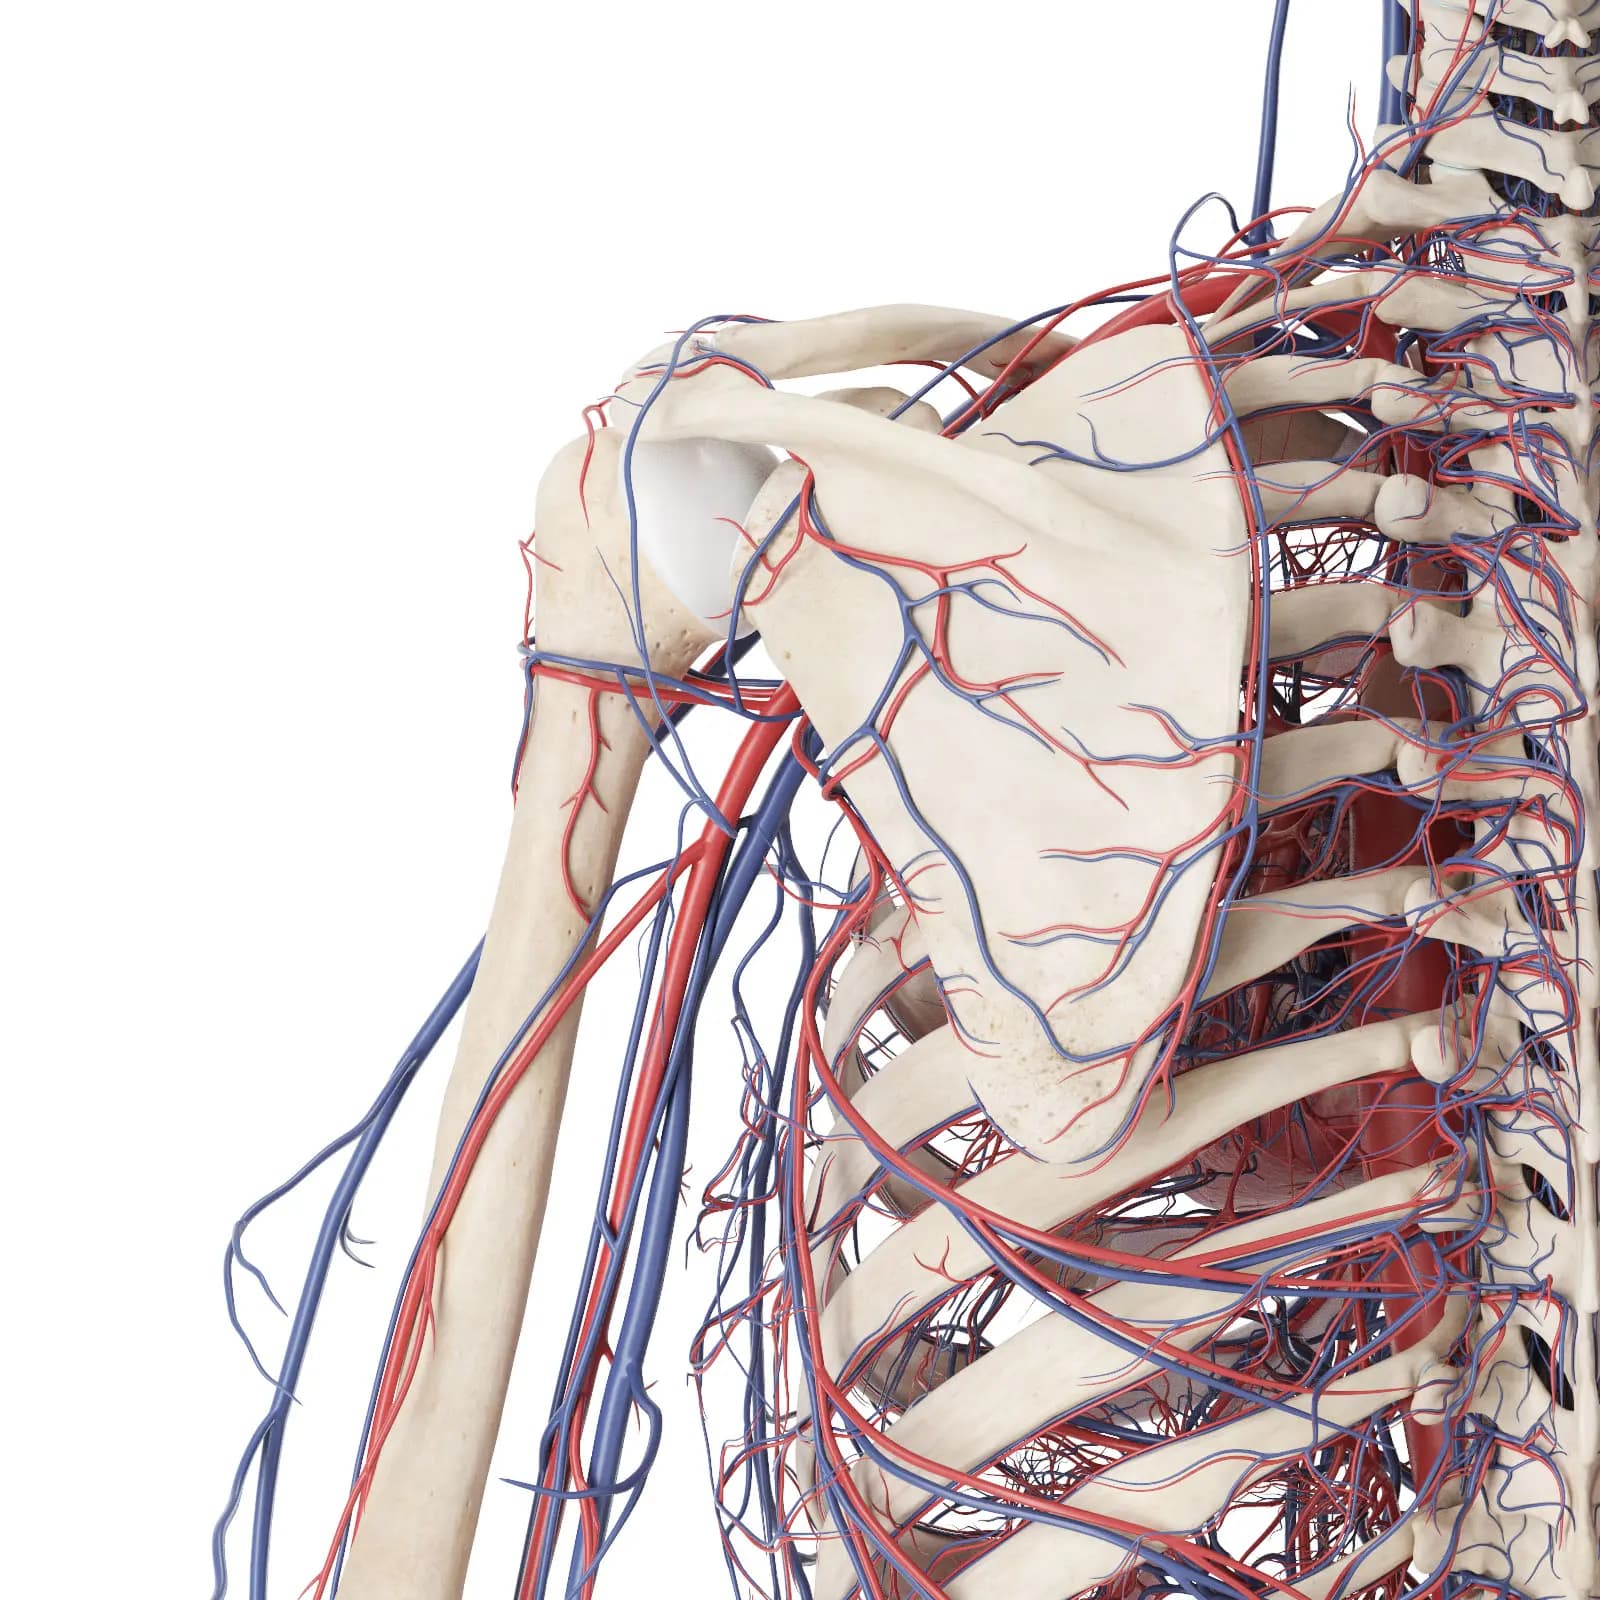

3d Rendered Medical Illustration Of The Vascular System Of The Shoulder And Upper Back